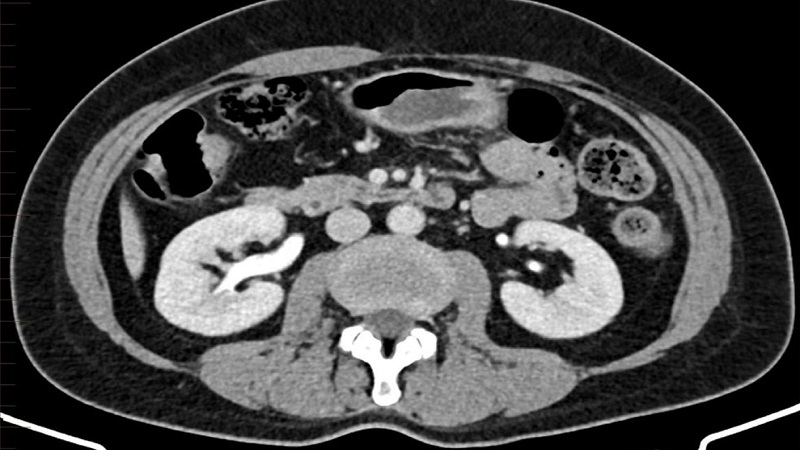

Chụp CT Scanner hệ tiết niệu sử dụng tia phóng xạ liều thấp và thuốc cản quang để kiểm tra, đánh giá hiện trạng của các cơ quan bài tiết nước tiểu như: Thận, niệu quản, bàng quang,...

Chụp CT Scanner hệ tiết niệu còn được biết đến với tên gọi quen thuộc hơn là chụp cắt lớp vi tính hệ tiết niệu. Phương pháp này sử dụng máy chiếu tia X và thuốc cản quang để làm rõ hình thái, đặc điểm cấu tạo và khả năng làm việc của các bộ phận cấu thành nên hệ tiết niệu. Điển hình là niệu quản, thận, bàng quang.

Khi chụp cắt lớp vi tính hệ bài tiết nước tiểu, tia X sẽ quét và tạo ra nhiều lát cắt hình ảnh ở hệ tiết niệu. Tùy vào từng dòng máy mà hình ảnh thu được có thể mô phỏng dạng 2D hoặc 3D. Kỹ thuật này là phương pháp không xâm lấn nhưng vẫn có thể can thiệp sâu và nhận biết chi tiết về khu vực kiểm tra. Đặc biệt nó còn có khả năng đo tỷ trọng, phân biệt rạch ròi các chất có hình thức dễ gây nhầm lẫn như dịch, máu, vôi hóa mô mỡ,...

Ngoài ra, cũng nhờ khả năng nhuộm màu cực hiệu quả của thuốc cản quang mà chuyên viên y tế có thể phân định rạch ròi các cấu trúc, khảo sát tốt hệ mạch máu thận, phát hiện tổn thương trong phạm vi cực nhỏ (1 - 2mm).